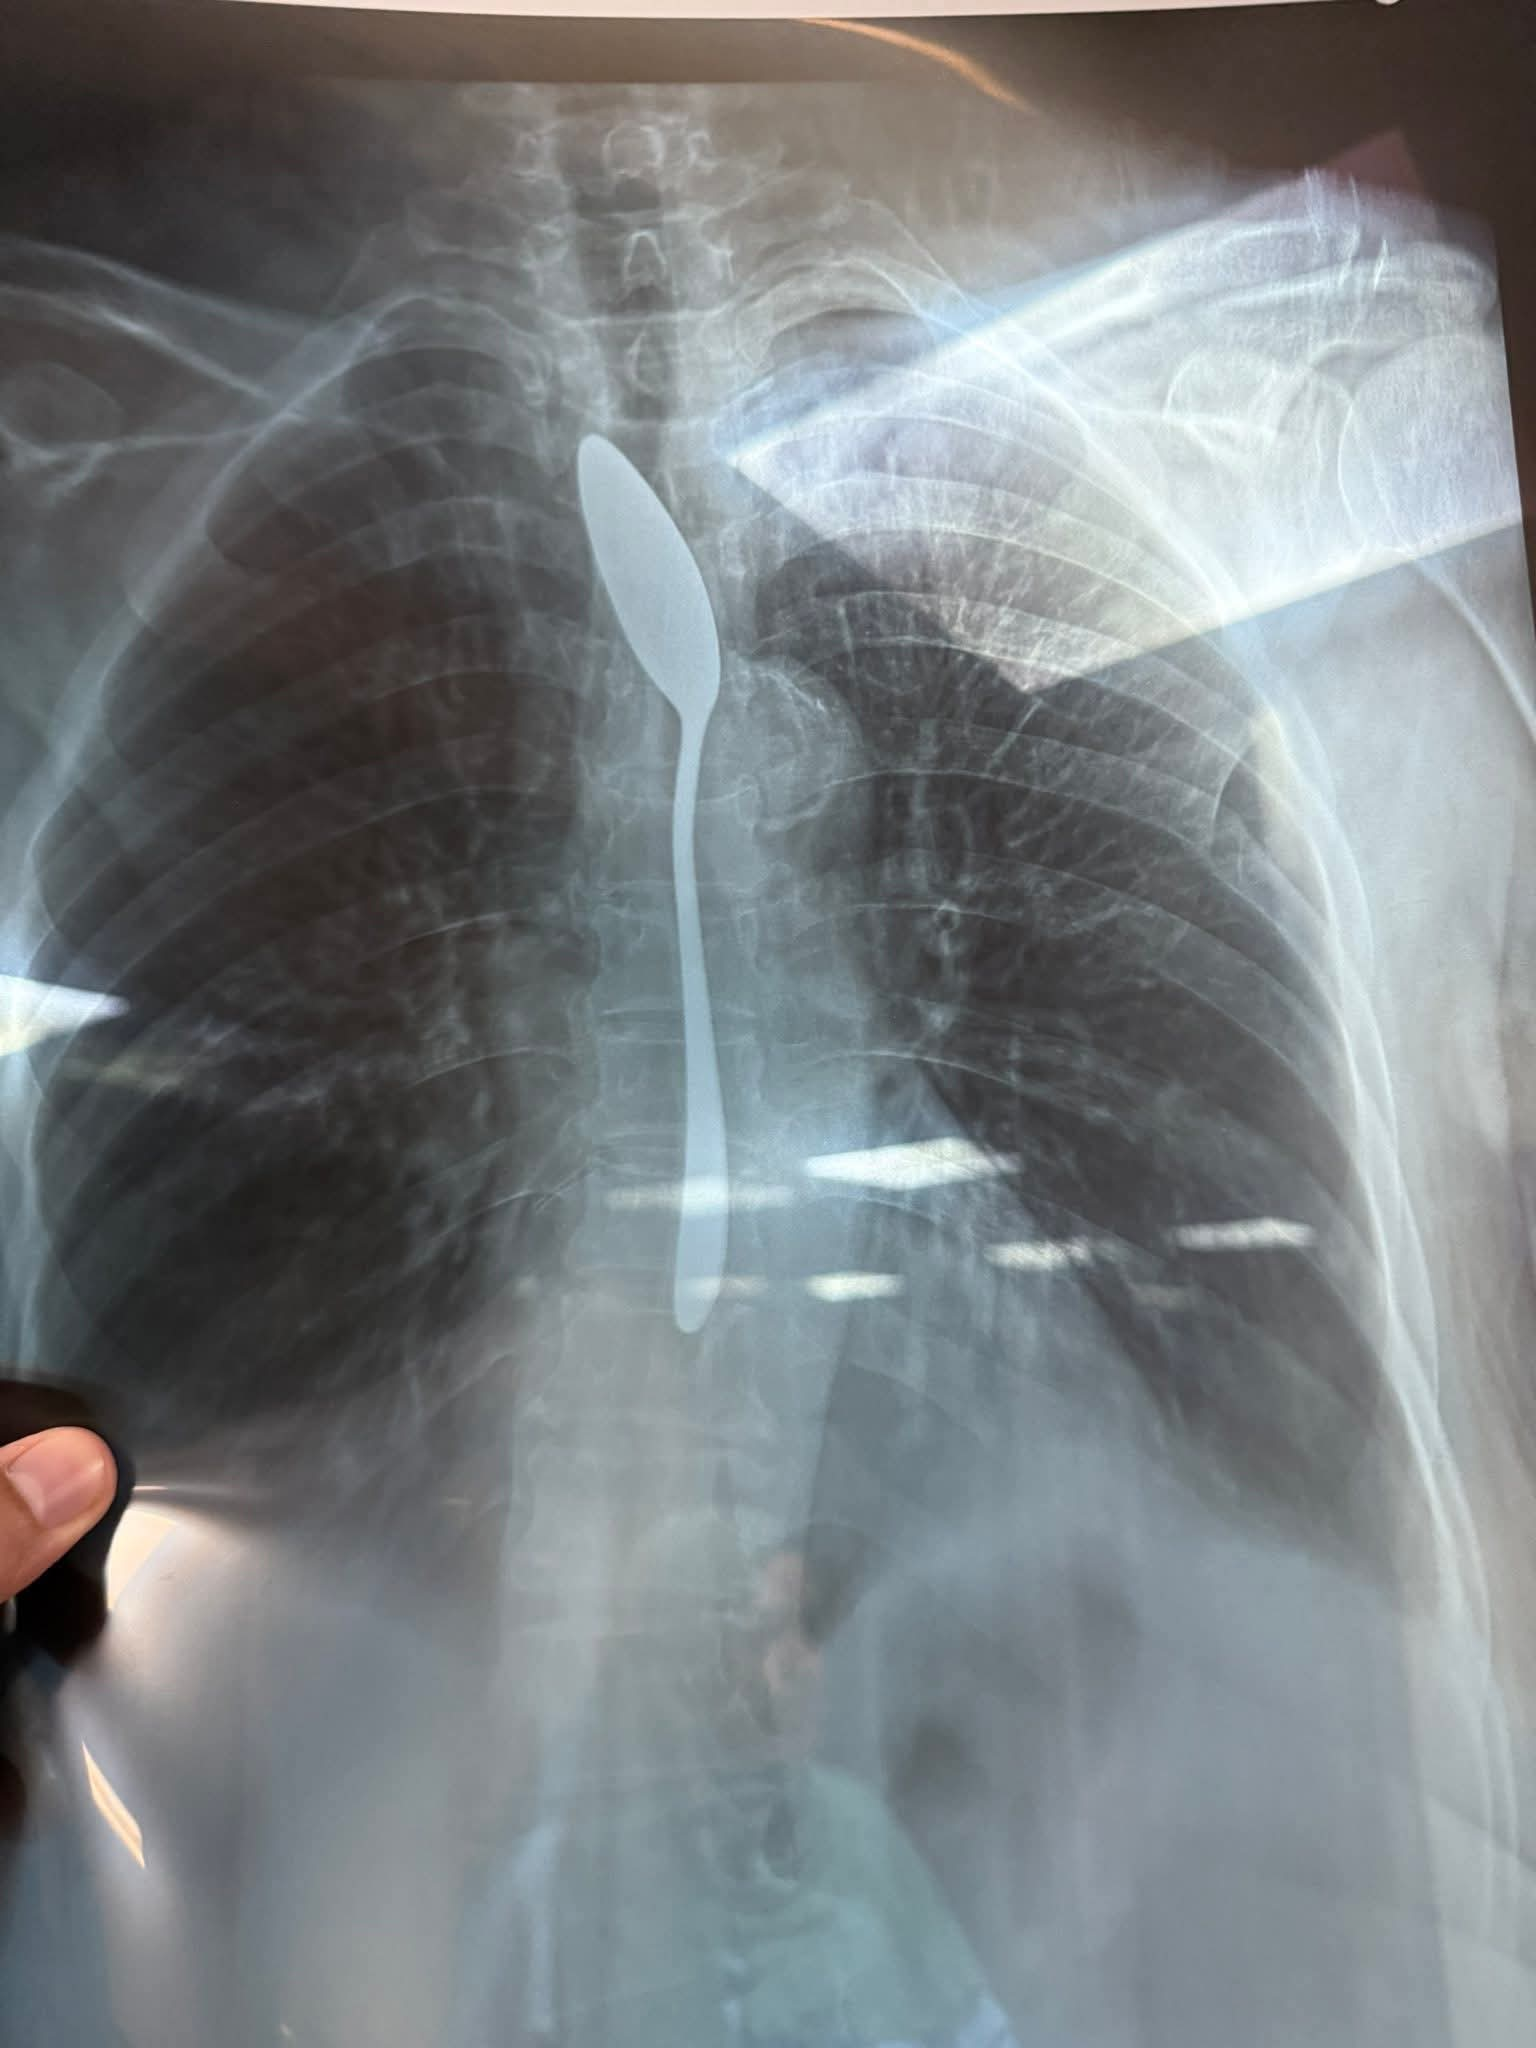

بدأت تفاصيل الحادثة عندما حضرت الابنة إلى قسم الطوارئ في حالة هلع، وهي تصرخ: “الحقونا يا دكاترة.. أمي بلعت معلقة شاي”، وبدا الأمر مستحيلا في البداية، قبل أن تكشف الأشعة المفاجأة الكبرى، حيث تبين وجود المعلقة بالفعل مستقرة داخل المريء.

وأكد الدكتور أحمد شهاب، أحد أطباء الطوارئ بالمستشفى، أن الفريق الطبي لم يصدق الأمر إلا بعد ظهور الأشعة بوضوح، ليتم على الفور تجهيز المريضة للتدخل الجراحي العاجل.